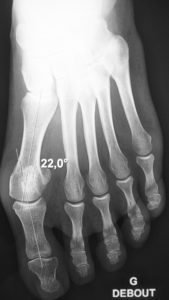

One of the pillars of modern hallux valgus surgery are the osteotomies. They are bone cuts performed by the surgeon to reorient the axis of the foot. They allow first metatarsal straightening and erase bone protrusion.

The osteotomies in open surgery are mostly of the “scarf” type or “chevron” type. To fix the bones in their new orientation, hardware is implanted : screws, staples, wires. The most often they are not necessarily to be removed as these implants are buried deep in the bone and perfectly well tolerated.